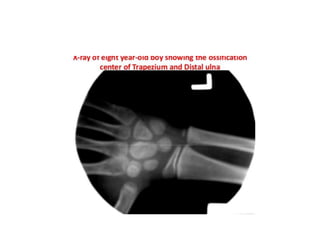

Pre-puberty • Females:2 years to 7 years of age • Males: 3 years to 9 years of age • Assessments of skeletal maturity in pre-pubertal children are primarily based on the epiphyseal size of the phalanges as they relate to the adjacent metaphyses

• During thisstage of development, the ossification centers for the epiphyses increase in width and thickness, and eventually assume a transverse diameter as wide as the metaphyses. • More weight is given to the size of the epiphyses in the distal phalanges than to that in the middle phalanges, and even less to that in the proximal phalanges

• Depiction ofthe progressive growth of the width of the epiphyses, which, during this stage of development, become as wide as the metaphyses

• The epiphysisof the ulna and all carpal bones, with the exception of the pisiform, usually become recognizable before puberty. • However, these ossification centers, like those of the metacarpals, are less reliable indicators of bone age at this stage of life.